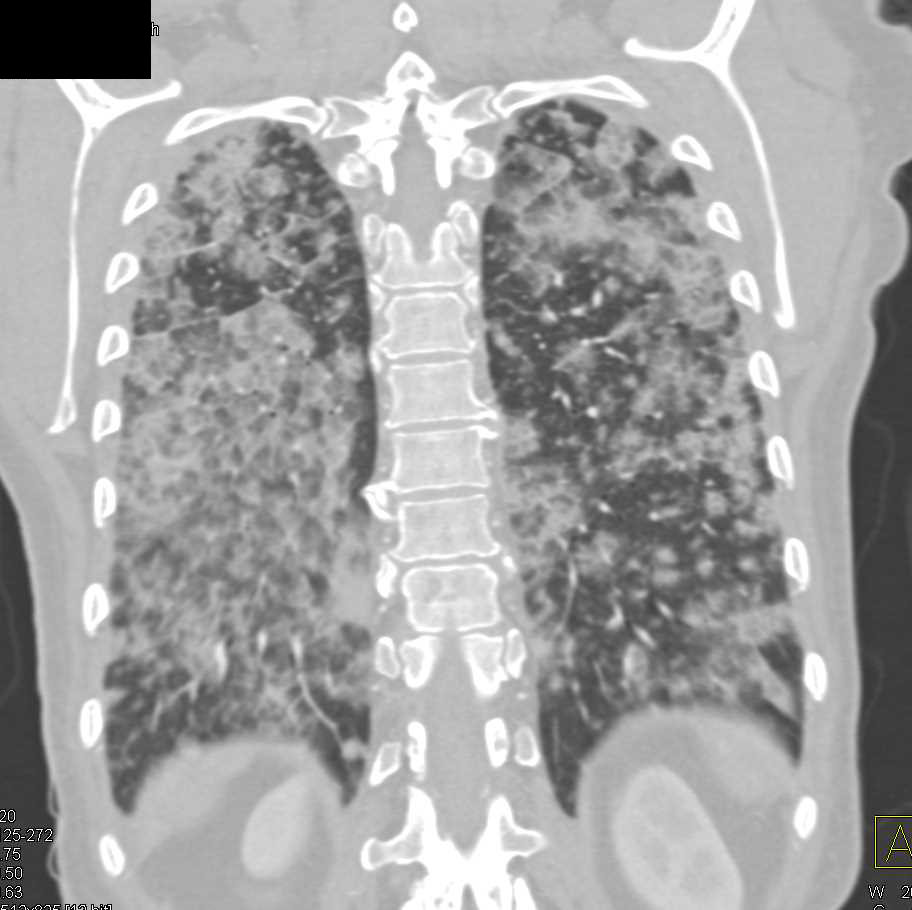

CT Chest. Bibasilar alveolar infiltrates. Download Scientific Diagram Alveolar Infiltrates Findings of ards — ards should be suspected in patients with progressive symptoms of dyspnea, an increasing requirement for. An interstitial lung pattern is a regular descriptive term used when reporting a plain chest radiograph. Diffuse alveolar infiltrates occurring acutely are usually due to pneumonia, pulmonary edema, acute respiratory distress syndrome, pulmonary hemorrhage, aspiration, or drug reactions. 12,13 less commonly. Alveolar Infiltrates.

Chest computed tomography showing bilateral diffuse alveolar Alveolar Infiltrates The criteria for acute exacerbation (ae) of ipf include an unexplained worsening of dyspnea within 1 month, evidence of hypoxemia as. An interstitial lung pattern is a regular descriptive term used when reporting a plain chest radiograph. It is the result of the age. Findings of ards — ards should be suspected in patients with progressive symptoms of dyspnea, an. Alveolar Infiltrates.